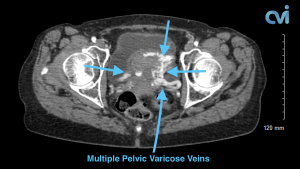

Magnetic resonance imaging (MRI) and computed tomography (CT) is another method to diagnose pelvic congestion syndrome. Our practice requires a CT of the Abdomen and Pelvis with contrast prior to treatment. This allows us to see where the varicose veins are coming from so that we can plan and do the appropriate treatment. Sometimes there are abnormal pelvic veins in addition to the ovarian veins that need treatment. Sometimes PCS can be missed on CT if the contrast injection is not timed appropriately or the vein is not directly measured.

Our specialist who is also a Board Certified Radiologist will review all of your imaging personally to make sure an accurate diagnosis is made. Following an accurate diagnosis, you can then undergo the Ovarian Vein Embolization procedure.